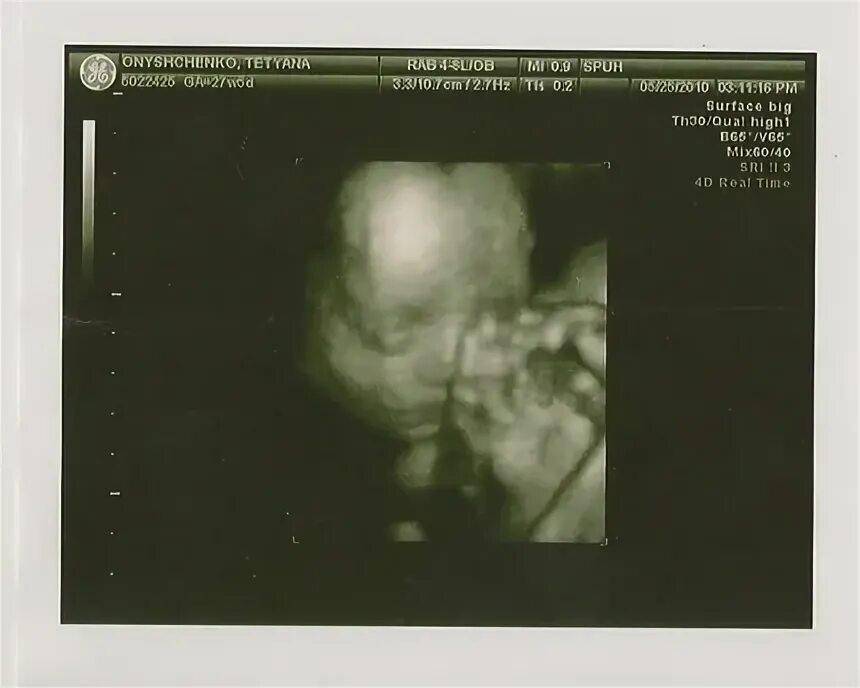

Узи 6 месяцев